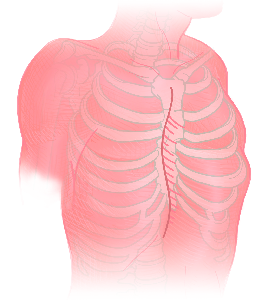

Detailreiche Fotografien aus der medizinischen Praxis ergänzen die Texte; moderne, genaue,

wissenschaftliche Zeichnungen geben Einblick in die Anatomie und die Funktion der Lunge und

anderer Organe.